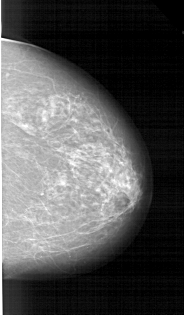

A_1214_1.RIGHT_MLO

RIGHT_MLO LINES 6031 PIXELS_PER_LINE 3811 BITS_PER_PIXEL 12 RESOLUTION 43.5 NON_OVERLAY